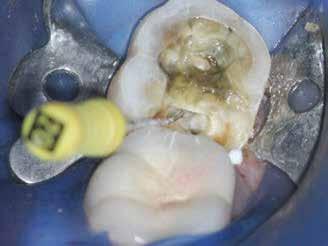

Klinikai vizsgálat során vertikális kopogtatási érzékenységet jelzett. A fog körül mérhető szondázási mélység és a fogmobilitás fiziológiás volt. A CBCT-felvételen nem észleltünk a csontos regeneráció megindulására utaló jeleket (1. a–c. ábrák). A korábban gyökérkezelt, gyökértömött és revideált 3.6-os fog esetében az alábbi diagnózis került felállításra: periodontitis periapicalis symptomatica. A panaszokat okozó fog további ellátása során navigált endodonciai mikrosebészetet kívántunk alkalmazni. Az alsó állcsontról intraorális szkent (TRIOS, 3Shape) készítettünk, és a felszíni topográfiát tartalmazó STL fájlt, valamint a CBCT-felvétel készítése során nyert DICOM fájlokat a Blue Sky Bio szoftver segítségével egyesítettük. A sebészi sablon megtervezésére az így kapott háromdimenziós képet használtuk. A sablon kialakítása során arra törekedtünk, hogy a sablon egyértelműen meghatározza a gyökércsúcsi terület eléréséhez szükséges csontablak határait (1. d. ábra)

A beavatkozás során helyi érzéstelenítésben teljes vastagságú mucoperiostealis lebenyt képeztünk, és a sablon segítségével bejelöltük a preparálandó csontablak határait. Az ablak széleinek megfelelően Piezotome CUBE LED kézi-darabbal (ACTEON) a kortikális teljes vastagságában vágást ejtettünk, majd az így kapott csontlemezt (ablakot) eltávolítottuk (1. e–h. ábra), és ezt követően steril fiziológiás sóoldatba helyeztük. A rezekció elvégzését követően (1. i. ábra) a mezialis csatornákat ultrahangos eszközök segítségével (NSK) retrográd irányból preparáltuk, majd az így kialakított mélyedésbe retrográd gyökértömést készítettünk. A tömés anyagául az EndoSequence BC RRM Fast Set Putty-t (Brasseler) választottuk. A tömés elkészítését követően a csontablakot visszaillesztettük, és a stabilizálása érdekében a vágásoknak megfelelően kialakult résekbe kollagén szivacsokat (Collagen Tape, Zimmer Biomet) helyeztünk (1. j-k. ábra). A lebenyt 6/0-s Prolene varratokkal (Corpaul) rögzítettük.